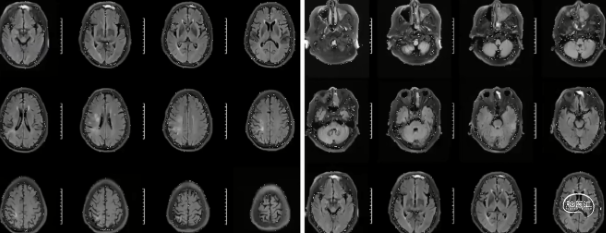

HR-MRI:右侧颈内动脉起始处偏心斑块,管腔重度狭窄,增强可见明显强化

HR-MRI:

3D-SPACE示,①右侧颈内动脉、右侧大脑前动脉A1段、右侧大脑中动脉管壁增厚,考虑动脉粥样硬化并不稳定斑块形成可能,②左侧颈内动脉交通段、左侧大脑中动脉、双侧大脑后动脉、双侧椎动脉V4段动脉粥样硬化改变,以上,请结合临床及其他检查协诊